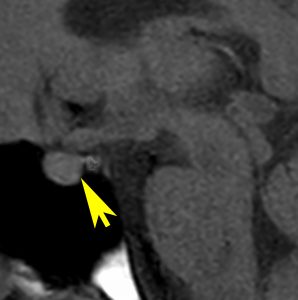

尿崩症にて発症した2年後にようやく小さなneurohypophyseal germinomaを発見された9歳女児例です。術前のT1強調画像では下垂体後葉のbrightnessが消失し,下垂体柄が腫大しています(左側)。ガドリニウムで腫瘍部分が増強されますが前葉よりは低信号となっています(右側)。経蝶形骨洞生検術で確定診断を得た後に,シスプラチンとエトポシドを1コース投与したところ腫瘍は完全消失しました。3コース後に24Gy12分割の放射線治療を加え再発はありません。残っていた下垂体前葉機能は治療後に少し改善しました。生検術では,トルコ鞍底を開けて下垂体後葉の下部を目標にして小さな組織採取をします。GHDがあっても前葉にはmassとしての腫瘍が無いと考えた方がいいでしょう。

血清HCGが2.1mIU/ml,尿崩症で発症した思春期男児です。石灰化はありませんし,脂肪組織なども混在しません。生検術をしなくてもgerminomaと診断できます。でも簡単なので,経鼻的な生検術を行った方がいいです。

この例は18歳,HCG 0.1mIU/ml,尿崩症で発症しました。神経下垂体ジャーミノーマなので,下垂体前葉のみが残って後葉から視床下部が腫瘍化しています。よくよく見ると松果体にもごく小さな腫瘍があります。右のCISS画像で松果体の腫瘍化が明瞭です。